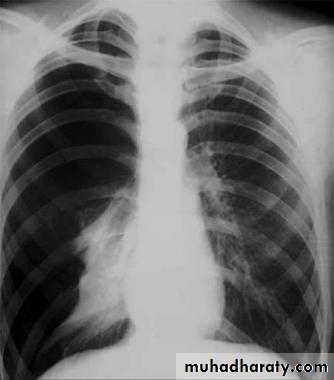

X-ray tension pneumothorax

Pneumothorax

A: before treatmentB: after treatment